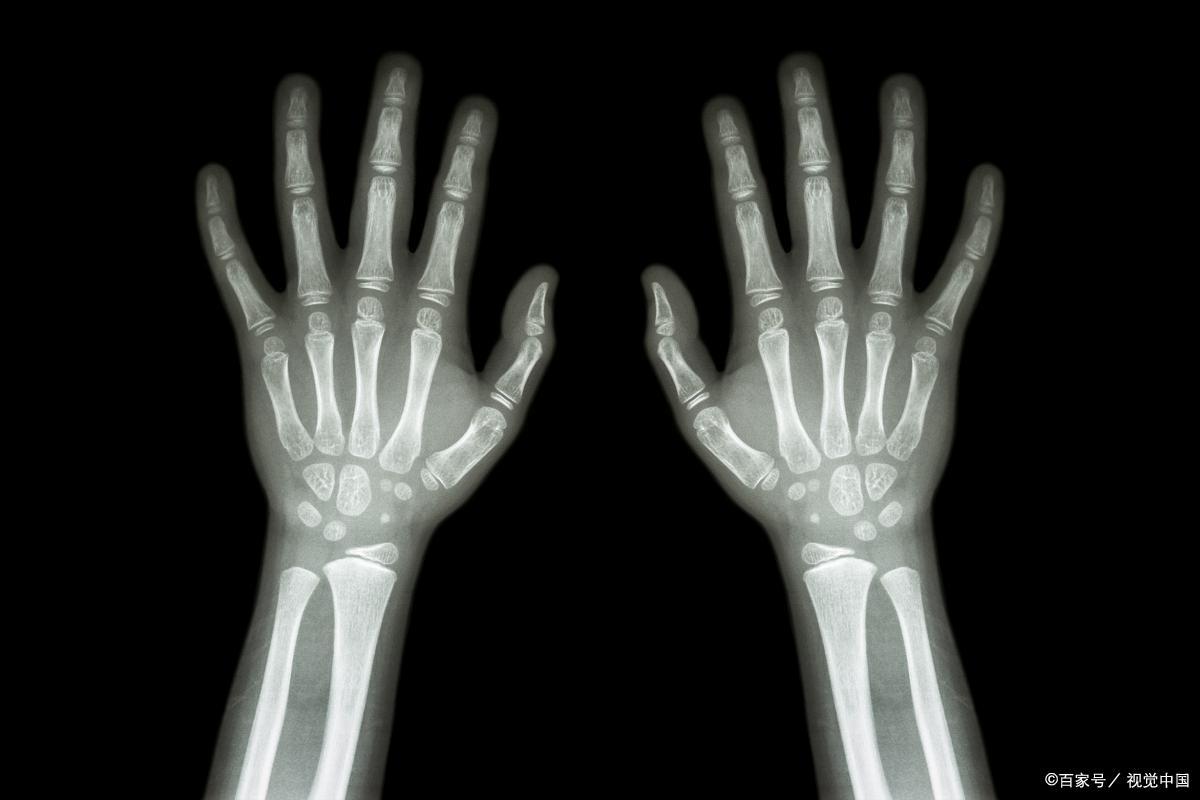

1、检查骨龄可以完全预测身高

骨龄月预测可供参考,骨骼发育不仅受遗传因素的影响,还受内分泌激素、炎症、营养状态、外力等因素的影响;

因此,单次骨龄检测只能反映检测时间节点的发育情况,仅靠骨龄是无法准确预测未来身高的,我们需要结合性别、遗传背景、发育年龄、当前身高和生长速度进行综合分析。

此外,不建议在孩子3岁前进行常规骨龄检测。